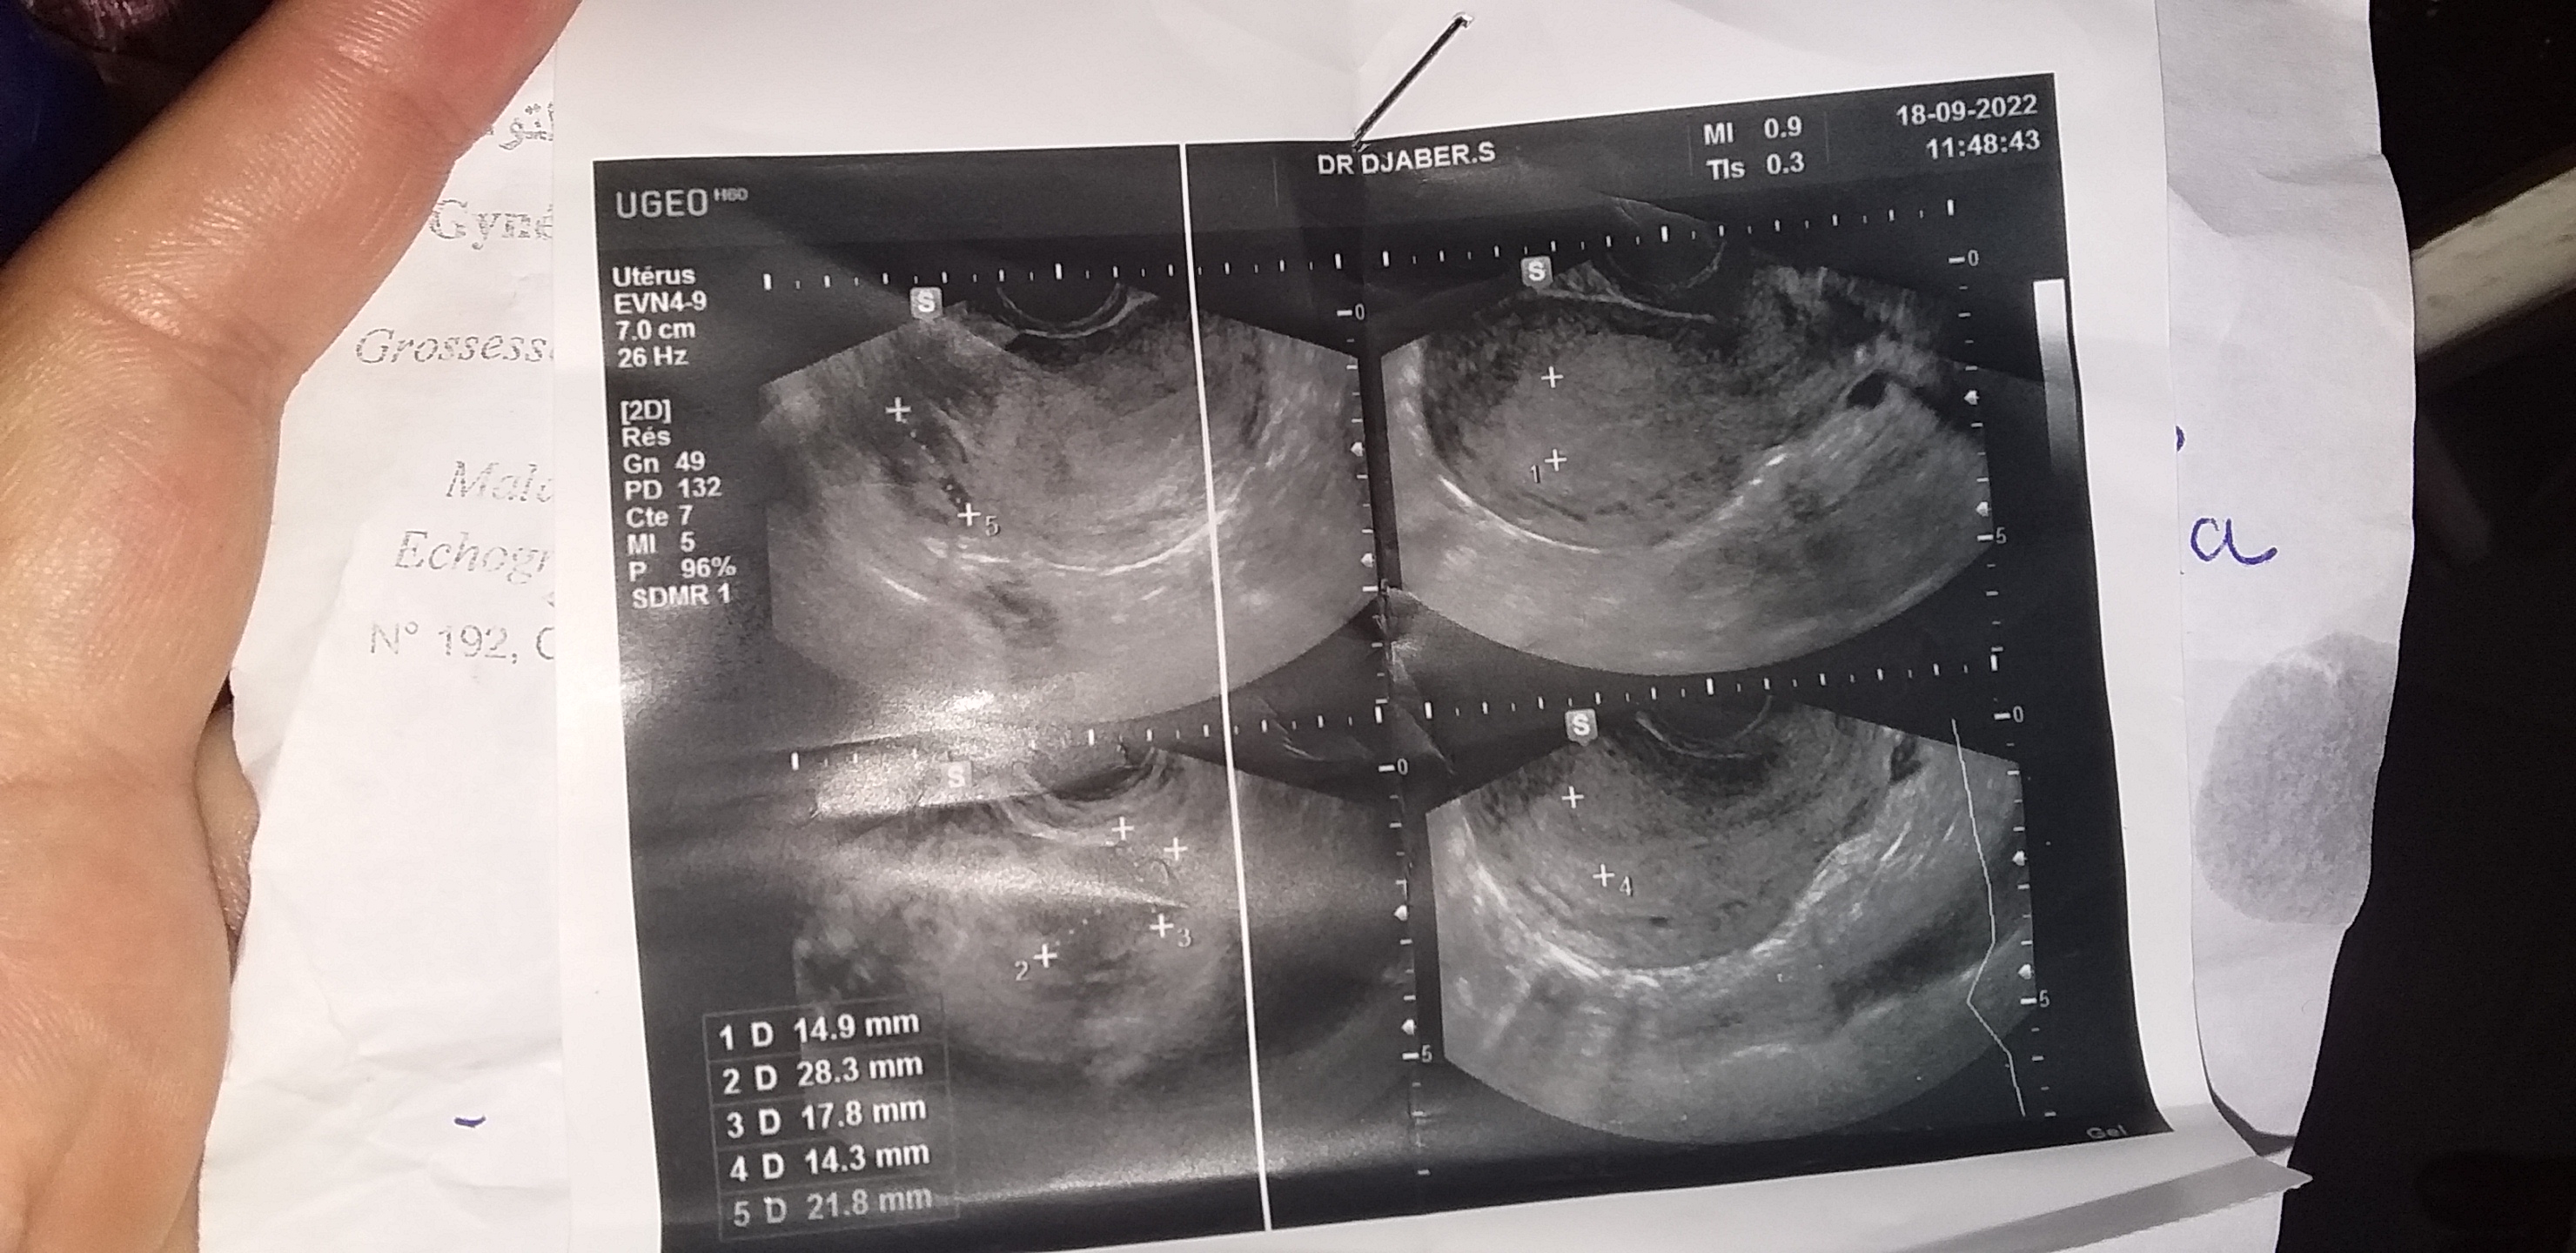

قراءة رموز السونار من فضلكم